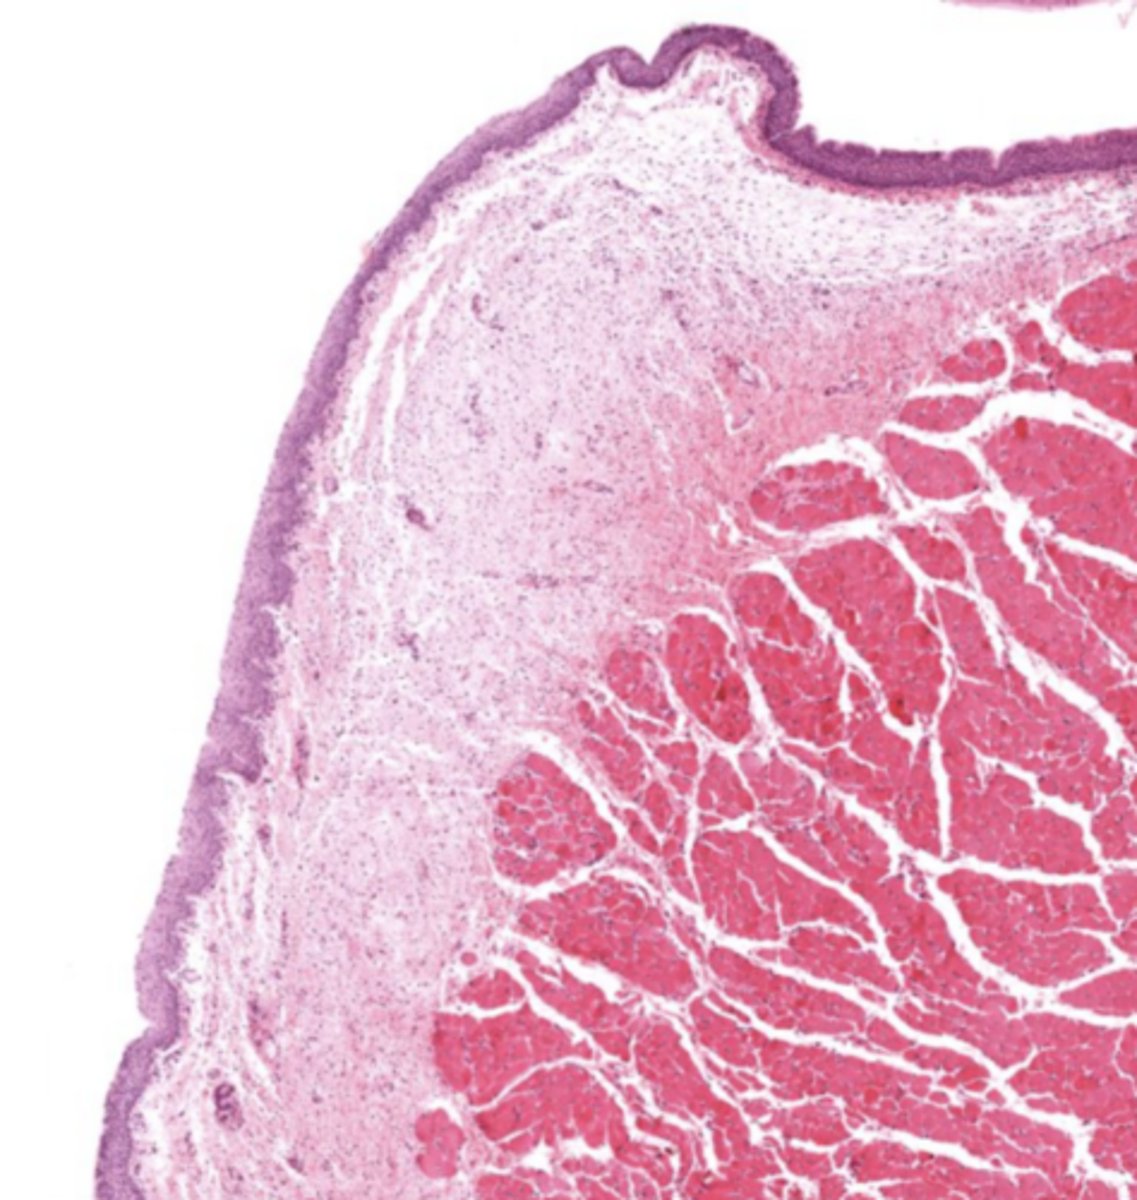

What tissue composes the vestibular folds?

Loose connective tissue with glands and lymphoid aggregations.

What epithelium covers vestibular folds?

Respiratory epithelium.

Understand how the epithelium changes from epiglottis to treachea`

False vocal cords - pseudostra. cillated epithelium

False cords of the larynx

Identify the image

Larynx (voice box)

Identify the entire structure